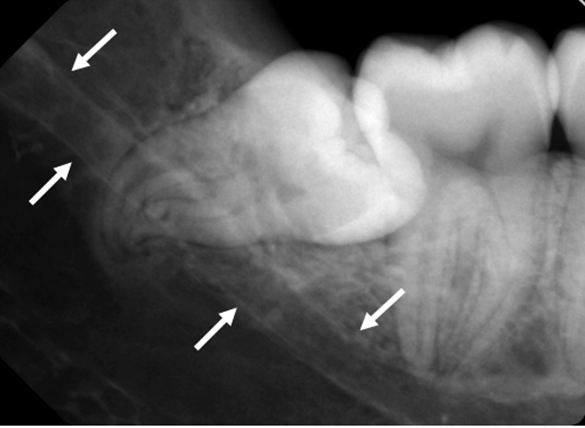

下顎管が歯根に重なっている場合には、他の放射線学的方法を使用する必要があります(7)。

図 3: 下顎管が歯 38 の根に重なっていることを示すパノラマレントゲン写真。